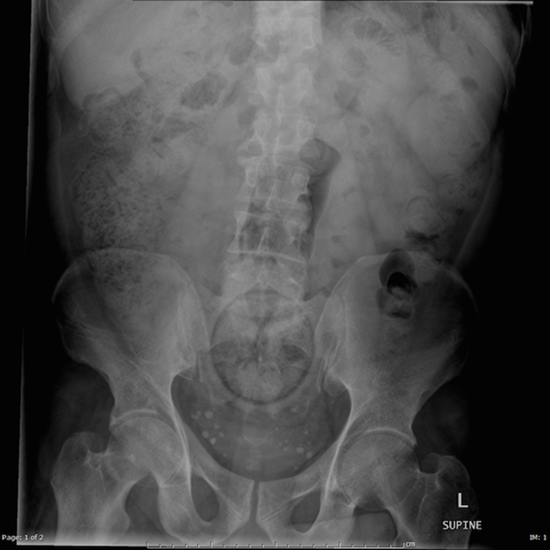

เหยือกเนยถั่ว